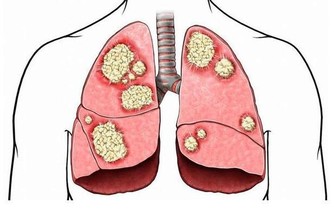

8 、咳嗽不止。

美國喬治城大學醫學院拉尼特·米歇里博士表示,

如果莫名其妙的咳嗽持續不斷,超過3—4周,就應該及時看醫生,有可能是肺癌或喉癌的徵兆。

體重急劇下降、厭食、反覆腹瀉和便秘是最常見的肺癌、胃癌、腎癌及大腸癌症狀,對女性而言也可能是甲亢。

比如,長期腹痛是大腸癌的症狀,胸部疼痛可能是肺癌引起的,骨頭酸痛則可能是癌症轉移的症狀。